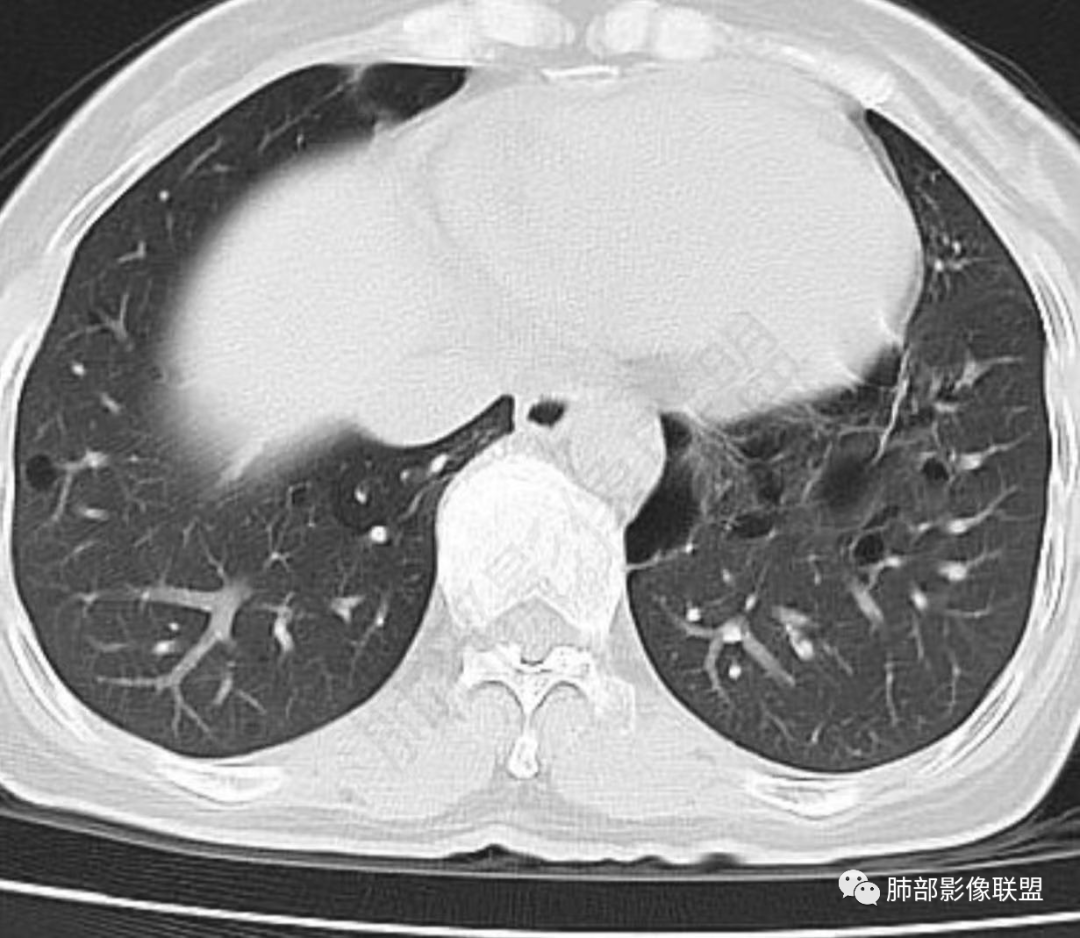

中年女性,否认肿瘤病史,双肺多发气囊,中下肺相对多发,考虑LIP,鉴别BHD综合征。

秦化君: 晨读 双肺不均匀散在多发囊状影,大小不等,部分囊形态欠规整,壁薄均匀,部分囊胸膜下平行。双肺少许斑片状磨玻璃影,边缘模糊。考虑BHD综合征。鉴别PCP,LIP。

红日初升: 中年女性,双肺多发气囊,背景干净,大小不一,下肺韧带旁较大,考虑BHD,鉴别LIP、LAM

玫: 晨读:女,49岁,双肺散在多发囊性病灶影,薄壁,部分层面病灶形态欠规整,右肺下叶少许磨玻璃影,边缘模糊,考虑LIP,鉴别BHD。

宇宙: 中年女性,两肺多发大小不等薄壁囊状影,两肺纵膈胸膜下分布明显,考虑BHD,鉴别LAM

放射线 (王秀仙): 双肺多发囊状影,大小不等,部分囊壁呈磨玻璃样,另双肺见斑片状磨玻璃影,边缘模糊。女性,考虑LIP,鉴别BHD

段建民: 双肺多发囊状影,多成圆形或三角形,囊壁薄且均匀,正常肺野内透过度尚可。双肺多发囊状影的鉴别,中心肺气肿,间隔旁肺气肿,PJP,支气管扩张,囊肿,支气管肺发育异常;LAM LIP PLCH BHD;囊腔腺癌,转移瘤,血播金葡菌……

本病例首先考虑BHD。

良孑: 两肺多发含气囊腔,大小不等,囊周见血管伴行,首选BHD,建议查双肾情况,鉴别Lam

这个病例目前影像特点,多囊,囊主要位于下肺,胸膜下及小叶核心为主

伴随少许索条,而且这些病灶与囊不一定有相关性

囊的分布,PLCH基本可以排除

囊壁薄且均匀,光滑,形态规则,基本除外恶性

单纯囊,无斑片及其他实性病灶,感染不支持,可能的是:LAM、BHD、LIP

从囊的分布、大小,BHD可能性可能大一些,但是LIP、LAM都可以这样表现,具体诊断应该是这三种之一,影像缩小到这里我觉得就差不多了,结合临床考虑就行,不支持靠影像强下结论。